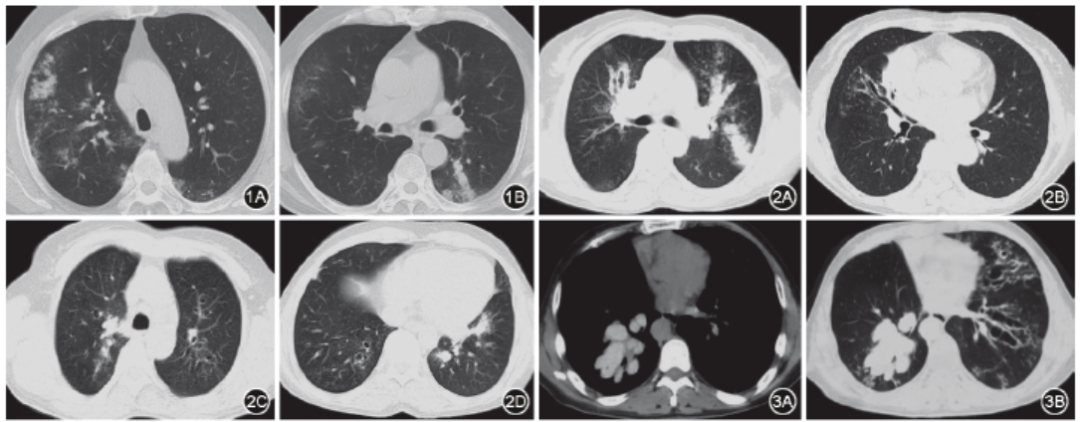

ABPA的影像学表现为肺部浸润影和实变影,肺浸润呈均质性斑片状、片状或点片状,不伴叶间隙移位,上中下肺部均可分布。可以表现为一过性、反复性、游走性异常及永久性异常(图1, 2, 3)。在急性加重期可表现为一过性影像学异常,而疾病缓解或控制后肺部浸润减少,但可见基础肺部病变。在疾病后期可出现持久的影像学异常。

ABPA具有一定特征性的其他影像学表现,包括黏液嵌塞(图1)、支气管扩张(图2)、小叶中心结节、马赛克征等。

气道黏液嵌塞在ABPA很常见,在胸部高分辨率CT(HRCT)上可表现为「牙膏征」或「指套征」[3]或「树芽征」(图1,图2C)。当黏液嵌塞发生在扭曲的支气管中,呈现出的阴影称为「牙膏征」;「指套征」的形成是由于支气管扩张并远端闭塞,扩张支气管腔内充满黏液导致的[40];外周细支气管黏液嵌塞可导致「树芽征」。气道黏液栓通常为低密度影,但约20%可表现为高密度影[30],即气道内黏液栓密度高于脊柱旁肌肉的HRCT值(图3A、3B)。高密度的气道黏液栓对于诊断ABPA具有较高的特异度,并且已经被证实与初始免疫反应的严重性以及急性加重的频率相关[41]。高密度黏液栓不同于「钙化」,需注意鉴别。

中心性支气管扩张曾作为ABPA的诊断标准之一,但其敏感度仅为37%,鉴别诊断价值有限[42]。支气管扩张常见于肺上叶,约在1/3患者可延伸至周围支气管,因此认为支气管扩张只是ABPA的表现之一,而非诊断所必需。但是在临床上表现为支气管扩张症的患者,需进行ABPA的排除诊断。

图1 1例变应性支气管肺曲霉病(ABPA)患者胸部CT表现 1A:双肺片状渗出影、树芽征,右上肺为著;1B:左下肺黏液嵌塞征(指套征或牙膏征)

图2 ABPA患者胸部CT的支气管扩张表现 2A:左上叶舌段和左下叶黏液栓;2B:右中叶中央性支气管扩张;2C:右上叶指套征;2D:右下叶囊状支气管扩张和左下叶黏液栓

图3 ABPA患者胸部CT的气道黏液栓表现 3A:胸部CT纵隔窗表现为高密度影的黏液栓;3B:同一层面肺窗显示右下肺黏液嵌塞征,左肺支气管扩张